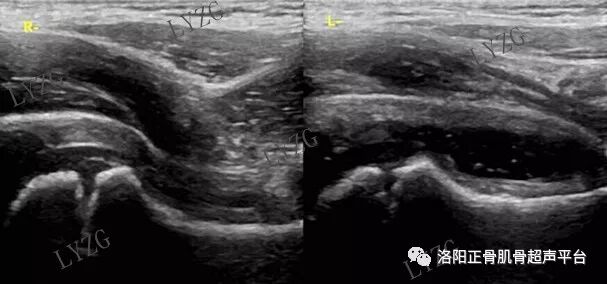

小儿髋关节滑膜炎超声表现

左侧髋关节前隐窝内积液并滑膜增生(呈不规则条带状)

右侧髋关节前隐窝内积液并滑膜增生(呈不规则团块状)